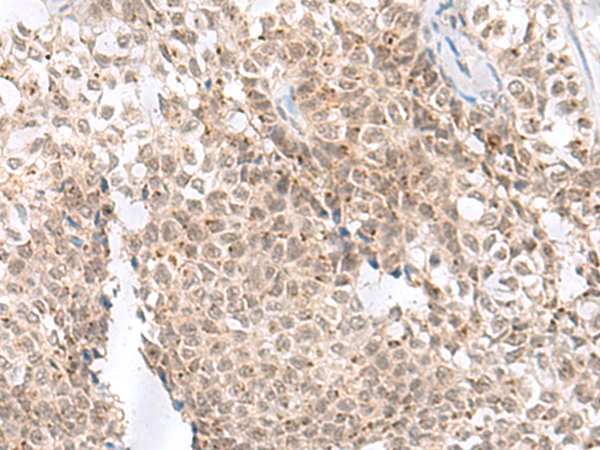

Immunohistochemistry analysis of paraffin-embedded Human ovarian cancer using Notch2 antibody. High-pressure and temperature Sodium Citrate pH 6.0 was used for antigen retrieval.